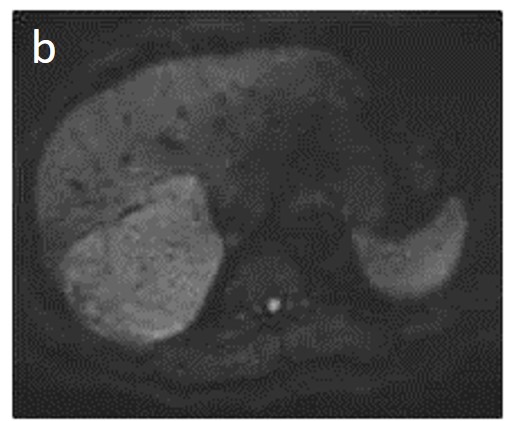

As mentioned before, the radiological hallmark that enables a confident non-histological diagnosis of HCC is the combination of hypervascularity on the arterial phase and hypoperfusion on the portal phase; as with CT, this “wash-in/wash-out” pattern is indispensable on MRI as well. According to the LI-RADS criteria, no lesion without hyperenhancement on the arterial phase can be definitely characterized as HCC; hyperenhancement has to be “non-rim”, i.e., not predominantly peripheral (in order to differentiate from metastases or cholangiocarcinoma) [51]. However, up to 40% of HCCs show no hypervascularity on the arterial phase, and these mainly represent early or poorly-differentiated HCCs [131,132]. Moreover, 40–60% of small HCCs lack wash-out during the portal phase [133,134] (Figure 10). Additional major and ancillary features are employed to help characterize the lesion and assign a LI-RADS category to it.

Figure 10. Evolution of a cirrhotic nodule into HCC. No suspicious lesions are identified on the T2 (a) and DWI (b) sequence of this 66-year-old man with cirrhosis due to hepatitis B infection. On the follow-up scan, performed 3 months later, increased T2 signal (c) is now observed in a nodule in segment V, which is associated with diffusion restriction (arrow) (d). After contrast administration, arterial enhancements (e) without delayed wash-out (f) are seen; absence of wash-out is frequent in early HCCs.